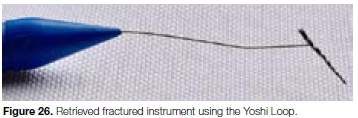

It was decided to use the Terauchi File Retrieval Kit (TFRFK) (Dental Cadre) to assist in removal of the fractured instrument. The 12 o'clock Micro-spoon ultrasonic tip (Figure 24) was used to penetrate through between the file and the canal wall in circular motion until it was noticed that the fractured file was loose in the canal. Considering the length of the fragment it was decided to attempt retrieval using the Yoshi Loop (Dental Cadre) (Figure 25a and 25b), a stainless steel micro-lasso that extends from the end of a stainless steel cannula attached to a handle with a retraction button for tightening the loop around the file segment.

Under magnification, the preformed loop was carefully placed around the exposed coronal aspect of the file. The loop was tightened around the fractured file by moving the retraction button on the loop system. The loop device was then used to slowly pull the loosened fragment from the root canal system (Figure 26). Figure 27 shows a magnified view of the retrieved instrument attached to the micro-lasso from the Yoshi Loop. Note that the tip of instrument is missing, indicating that the file tip must have been fractured in a previous clinical application prior to the case presented in this case report.